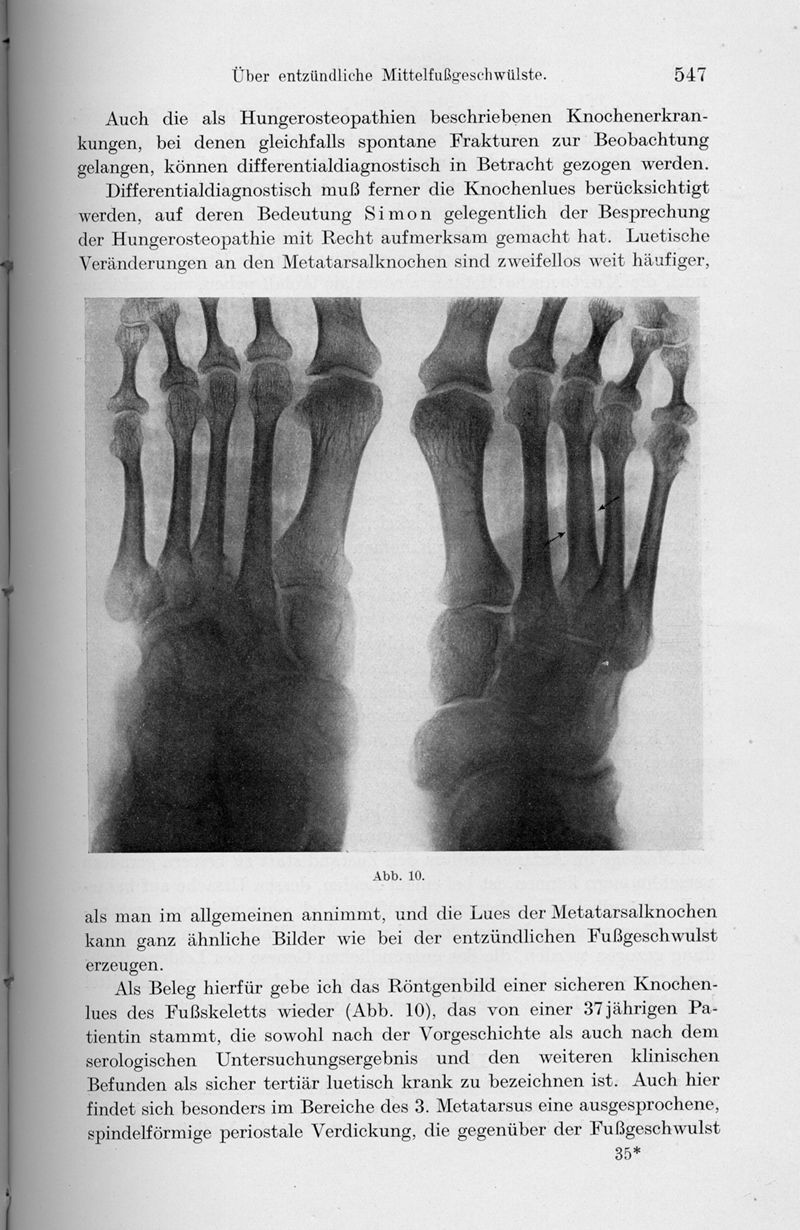

DEUTSCHLÄNDER, Carl Ernst Wilhelm.

In : Archiv für Klinische Chirurgie,

1921, Vol. 118, pp. 530-49

DEUTSCHLÄNDER, Carl Ernst Wilhelm.

In : Archiv für Klinische Chirurgie,

1921, Vol. 118, pp. 530-49